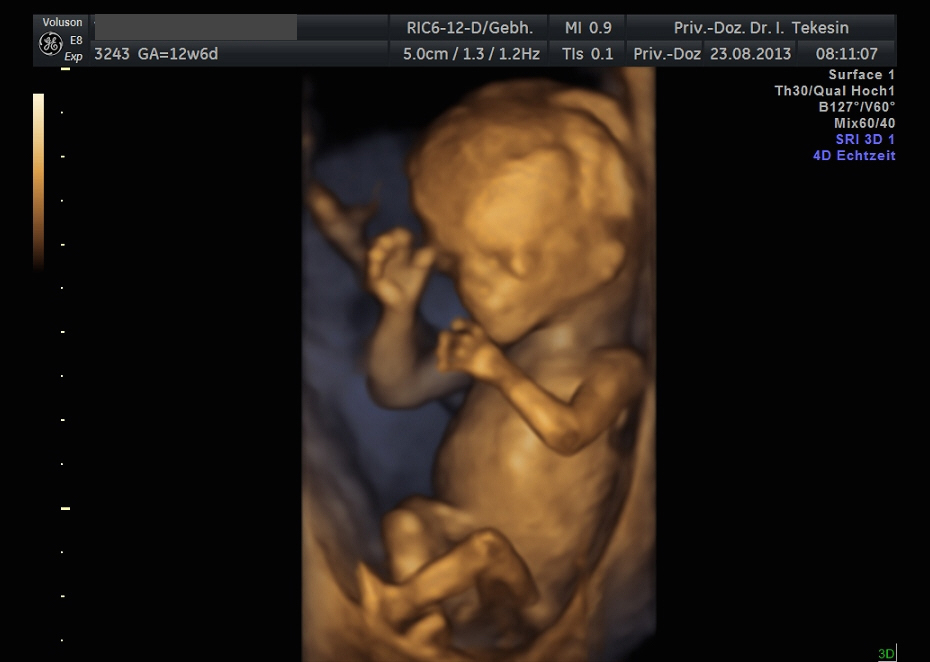

3D-/4D-Ultraschall (optional)

Immer mehr werdende Eltern interessieren sich für die faszinierenden Bilder, die dieses Verfahren liefert. Die plastische, dreidimensionale Darstellung der Oberfläche des Gesichts und anderer Körperregionen wird durch spezielle Bildrekonstruktion in schnellen Rechnern erreicht. Auch einzelne innere Organe oder „Gefäßbäume“ können von allen Seiten betrachtet werden. Viele dünne Schnittebenen (2D) werden zu einer gemeinsamen 3D-Sichtweise im Computer des Ultraschallgerätes zusammengeführt. Unter einem 4D-Ultraschall versteht man darüber hinaus eine 3D-Ultraschalluntersuchung unter Echtzeitbedingungen. Anstatt nur statische Bilder anzuzeigen, erfasst ein 4D-Ultraschall die Bewegungen des Kindes, weshalb er auch als „Live-3D-Ultraschall“ bezeichnet wird.

Diese Vorgehensweise ermöglicht äußerst realistische Bilder, bei denen sogar Gestik und Mimik des Kindes in bewegten Sequenzen festgehalten werden können. Die Untersuchung kann wie auch der normale Ultraschall während des gesamten Schwangerschaftszeitraums durchgeführt werden. Möchte man das Ungeborene komplett sehen, wird die 12. bis 16. Schwangerschaftswoche empfohlen, die Zeit zwischen der 28. und 33. Schwangerschaftswoche eignet sich besonders zur präzisen Darstellung einzelner Körperteile

Wir sehen in diesem modernen Verfahren in erster Linie eine ergänzende Maßnahme bei speziellen Fragestellungen bezüglich Herz, Gehirn oder Skelett und vor allem bei Verdacht auf eine fetale Besonderheit.

Kind in der 12. Woche (3D-Darstellung)

Kind in der 13. Woche (3D-Darstellung)